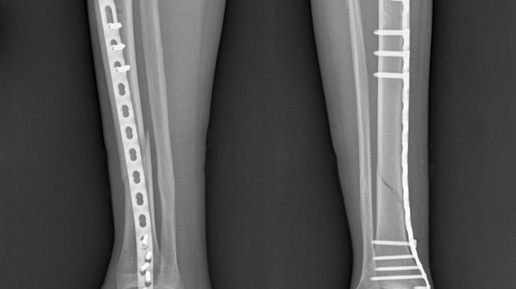

🏥 Травма хоккеиста: перелом голени Прекрасное субботнее утро, хорошее настроение и увлечение на уровне профессиональных достижений в хоккее. Да, именно хоккей познакомил нашего пациента с нами, врачами-травматологами-ортопедами Ильинской больницы. Это были последние минуты игры, когда во время торможения раздался хруст, который замер и словно повис в воздухе, будто колокольный звон. Пациент госпитализирован в стационар Ильинской больницы с диагнозом закрытый оскольчатый диафизарный перелом обеих костей голени...